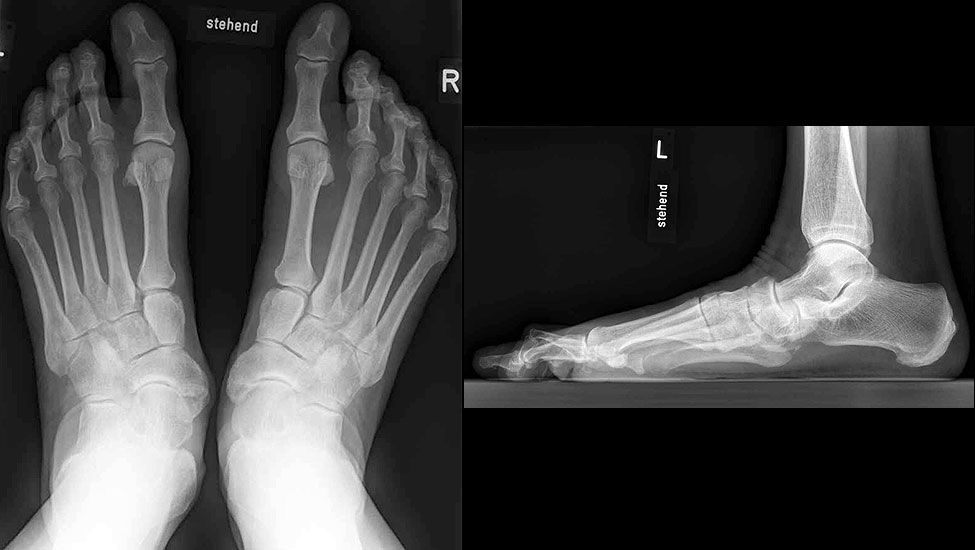

Stehende konventionelle Röntgenbilder eines Fußes mit Planovalgus Deformität Stadium II b dorsoplantar (dp) und seitlich. Auf der dp-Aufnahme zeigt sich die talo-calcaneare Divergenz, der gegenüber dem Kalkaneus nach anterior gleitende Talus und d

Abbildung 5

Stehende Aufnahmen des Fußes dorsoplantar (dp) und seitlich sowie des OSG anteroposterior (ap) sind die Grundlage der konventionellen Röntgendiagnostik (Abb. 5). Ergänzend werden gelegentlich die Rückfuβ-Alignement Aufnahme nach Saltzman 19 und Vergleichsaufnahmen der Gegenseite durchgeführt.

Der Talo-Metatarsale I Winkel bzw. die laterale talonaviculare Subluxation auf der stehenden dorsoplantaren Aufnahme des Fuβes dokumentieren das Ausmaβ des Vorfuβ abductus (Abb. 6 a,b). Ein dp Talo-Metatarsale I Winkel von > 10° (nach medial konvex) ist als pathologisch anzusehen. Mit der Bestimmung der talocalcanearen Divergenz (Abb. 6 c) erhält man ein Eindruck über das Ausmaβ des Rückfuβ valgus; eine leichte Divergenz bis ca. 12° gilt als physiologisch 20.

Auf der seitlichen, stehenden Aufnahme des Fußes wird ebenfalls der laterale Talo-Metatarsale I Winkel (Abb. 6 d) gemessen und so das kollabierte mediale Längsgewölbe dokumentiert. Auch hier gilt ein Talo-Metatarsale I Winkel von > 5° (nach plantar konvex) als pathologisch 21. Der Kollaps findet dabei meist im Talonaviculargelenk, seltener in der Naviculocuneiform-Gelenkreihe statt. Instabilität und Arthrose im 1. TMT sollten ausgeschlossen oder bei der Operationsplanung mit einbezogen werden. Weitere wichtige radiologische Messungen zur Beurteilung der Planovalgus-Statik und Progression der Deformität sind der laterale talo-calcaneare Winkel (Abb. 6 e) und der Abstand des Os cuneiforme-Unterrandes zum Untergrund (Abb. 6 f, Cuneiform height, 22. Eine anteriore Translation des Talus auf dem Kalkaneus findet man sowohl auf der ap, als auch auf der seitlichen Aufnahme des Fuβes mit Aufhebung der Cima-Linie.